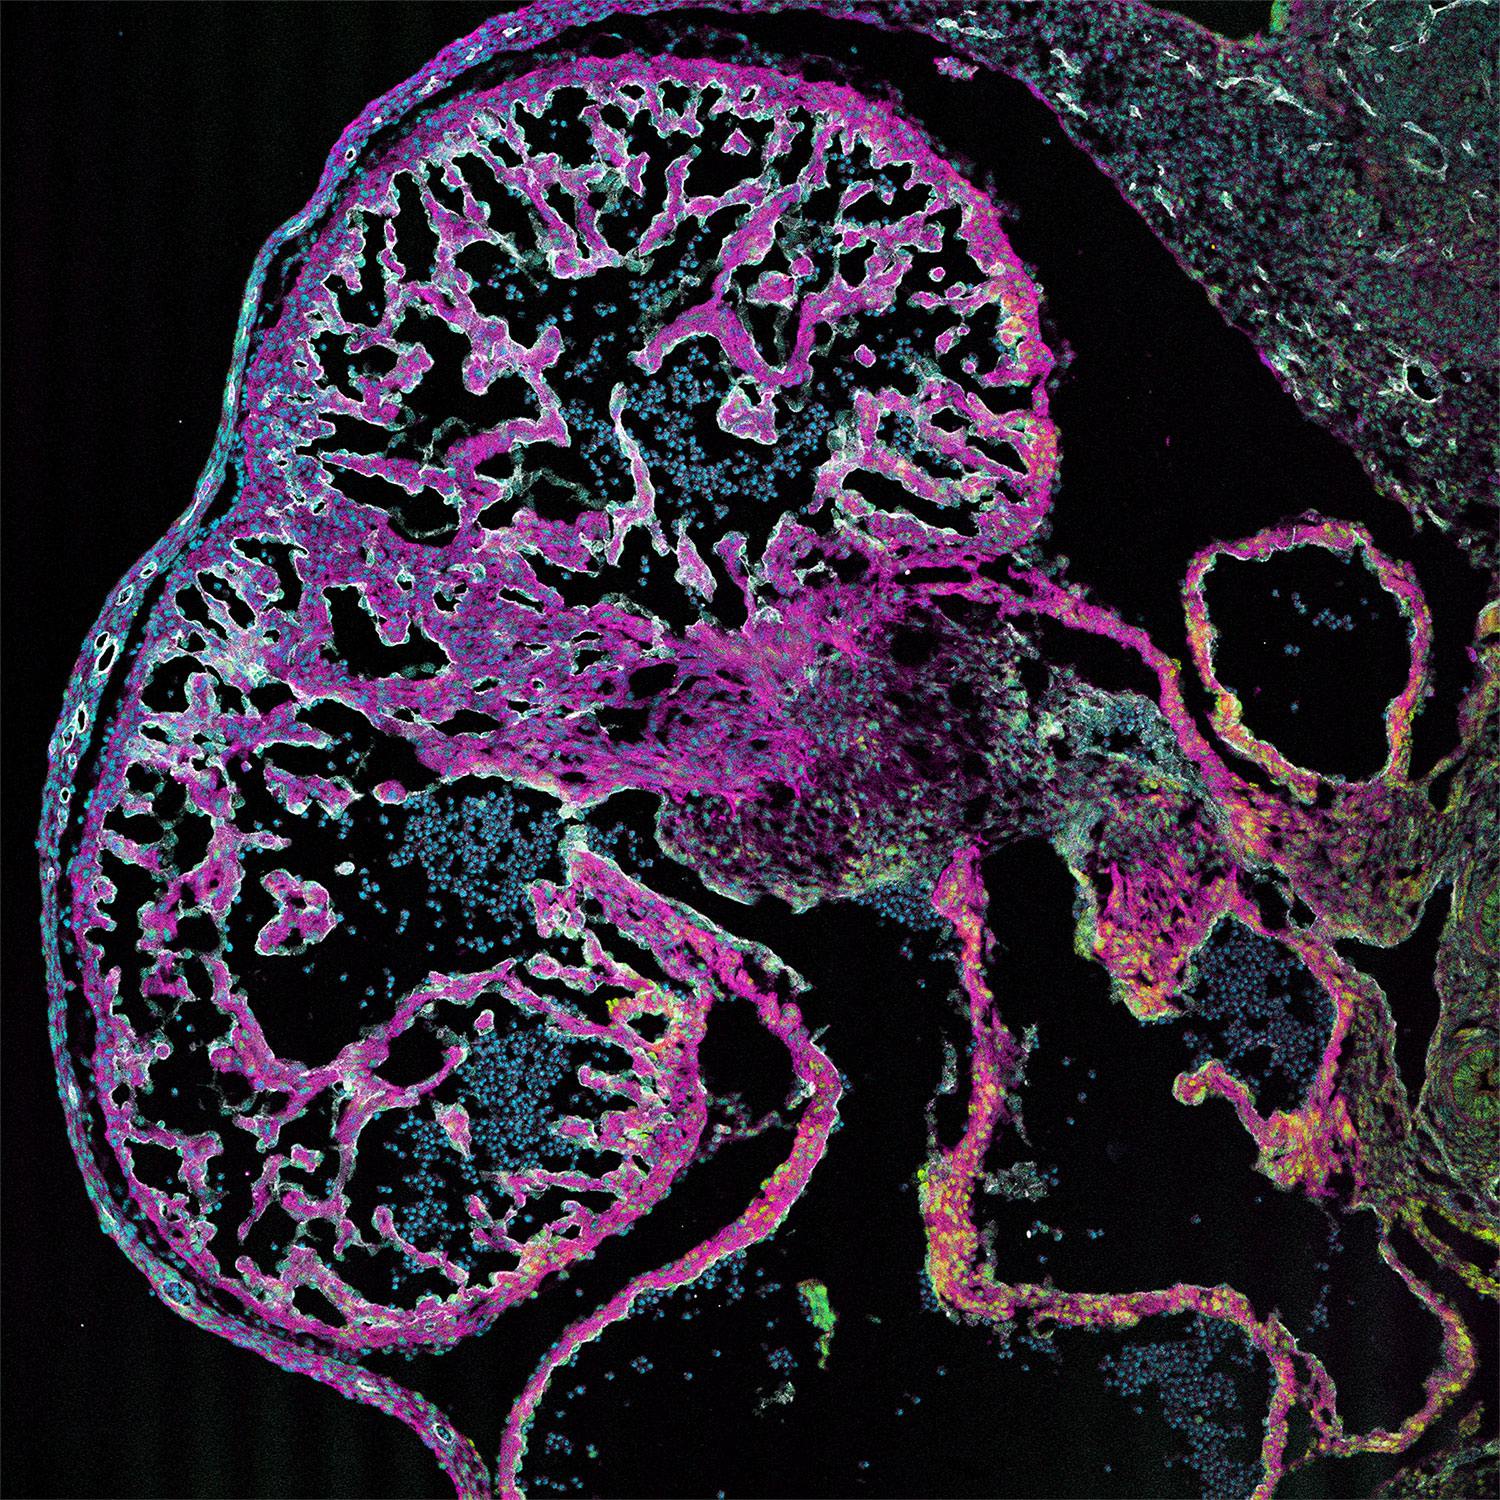

| Positive IF-Fro detected in | mouse heart tissue |

ARL13B, also named as ARL2L1, is a small ciliary G protein of the Ras superfamily. Localized in the cilia, it is required for cilium biogenesis and sonic hedgehog signaling. Defects in ARL13B are the cause of Joubert syndrome (JS) which is an autosomal recessive disorder characterized by a distinctive cerebellar malformation (PMID: 19906870). Arl13b is predicted to be a 48 kDa protein, and the 60 kDa band is likely to represent a modified form of Arl13b. ARL13B can be used to mark the cilia (PMID:22072986).